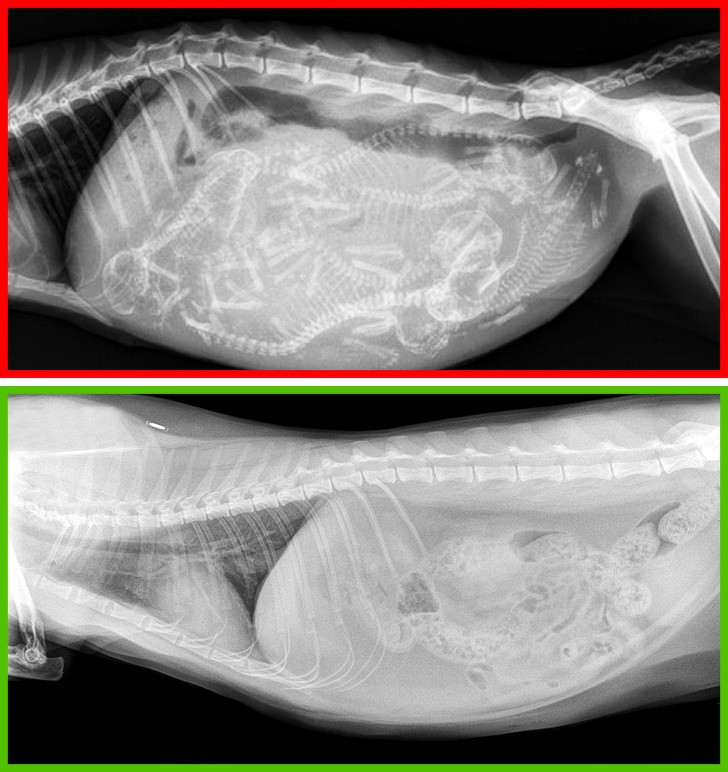

7. Không đi khám thường xuyên

Ngay cả những con mèo chưa bao giờ ra ngoài cũng nên được tiêm phòng. Cứ sau 6 tháng nên đưa mèo của bạn đến bác sĩ thú y để kiểm tra sức khỏe một lần.